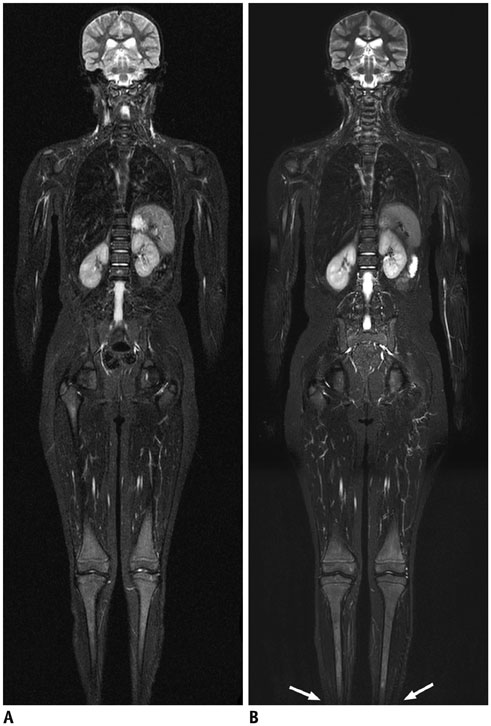

Doctors send patients in for MRI’s for all kinds of health concerns things like organs and the depth of bones can be scanned. They can see very deep details of things like nasal cavities to the whole brain. MRI’s can be used to detect if someone has abnormal tissue or a blockage in their veins. It can even be used to see the capillaries in the brain! I don’t know the medical science behind MRI’s but they can give layered information about the body. The radiologist will look at it and give a report to the doctors. Sometimes the specialist will look too.

One of the amazing things I read about was how In Canada they are working with MRI technology to help with treatments in Parkinson patients. It is still in the trial stages where they use the MRI that directs an ultrasound to open the blood-brain barrier to administer medications and treatments right in the brain. This is very key to helping treat certain conditions.